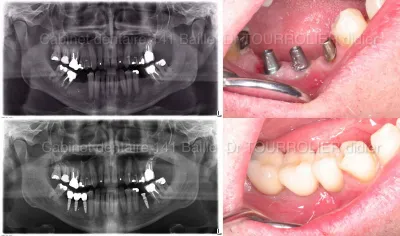

MCI et implantation totale

La MCI avec les implants cone morse -Cabinet 141 Baille 13005

La connectique cone morse est une véritable avancée en implantologie.Elle permet un enfouissement sous crestal des implants et une amélioration de la jonction implant pilier .Dans la MCI le switching platform permet une meilleure expression tissulaire postopératoire.